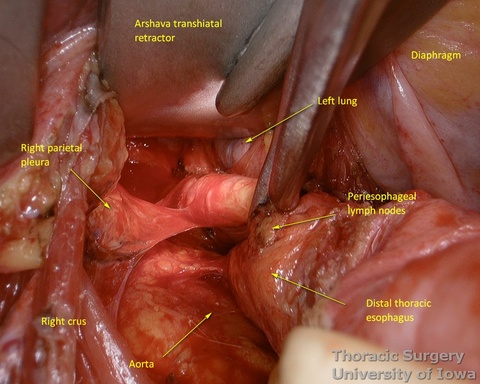

Transhiatal Phase

- The transhiatal retractor (See Arshava transhiatal retractor) is positioned in the esophageal hiatus.

- The illuminated transhiatal retractor is advanced into posterior mediastinum under direct vision

- The distal thoracic esophagus is visualized.

- Esophagus is circumferentially mobilized under direct vision using combination of sharp and blunt dissection up to the level of the carina.

- Right lateral esophageal “ligament” (attachments to the parietale pleura, pulmonary ligaments and branches of vagal nerves) is exposed are divided under direct vision

- Aorto-pleural and aorto-esophageal ligaments divide posterior mediastinum into peri-esophageal and peri-aortic (thoracic duct and azygos vein) compartments. They may be distinctly seen in some patients.

- Esophageal arteries (aorto-esophageal branches) and vagal nerves are divided under direct vision using the energy device.

- Periesophageal and subcarinal lymph nodes are dissected separately or en-block with the esophagus under direct vision.